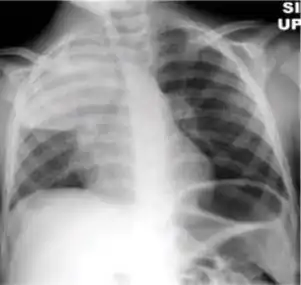

Chest x-ray of pleural thickening post-primary tuberculosis

1. Pleural thickening - Irregularity or abnormal prominence of the pleural margin, including apical capping (thickening of the pleura in the apical region). Pleural thickening can be calcified.

3. Blunting of costophrenic angle (in adults)—Loss of sharpness of one or both costophrenic angles. Blunting can be related to a small amount of fluid in the pleural space or to pleural thickening and, by itself, is a non-specific finding (except in children, when even minor blunting may suggest active TB). In contrast a large pleural effusion, or the presence of a significant amount of fluid in the pleural space, may be a sign of active TB at any age.